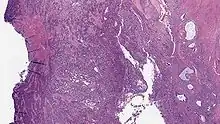

Endometrial Stromal Sarcoma, High-Grade

Undifferentiated uterine sarcoma, or undifferentiated (high-grade) endometrial stromal sarcoma, does not resemble normal endometrial stroma and behaves much more aggressively, frequently metastasizing. The differential includes leukemia, lymphoma, high-grade carcinoma, carcinosarcoma, and differentiated pure sarcomas.

• Monotonous ovoid cells to spindly cells with minimal cytoplasm.

• Prominent arterioles. Angiolymphatic invasion common.

• Up to 10-15 mitotic figures per 10 HPF in most active areas.

• Tongue-like infiltration between muscle bundles of myometrium.

• May exhibit myxoid, epithelioid and fibrous change.

• May have foam cells or hyalinization in the stroma.